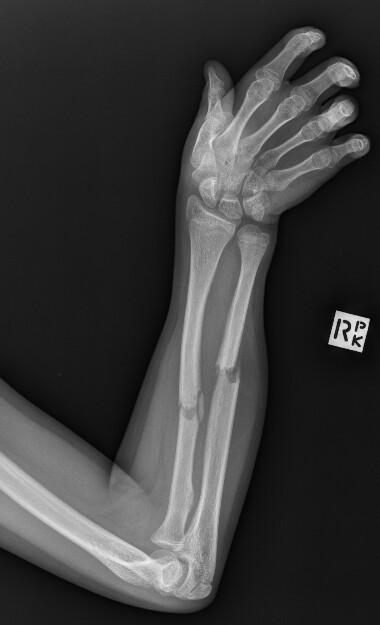

Andrew Baker, Radiopaedia.org. From the case rID: 69952

Fracture extrémité inférieure du radius

Non déplacée : immobilisation par attelle plâtrée antébrachio-palmaire pendant 4 à 6 semaines. Consultation orthopédique à J7.

Bascule postérieure (= fracture de Pouteau-Colles) : avis chirurgical. Réduction en flexion ulnaire et flexion palmaire et immobilisation par attelle plâtrée postérieure.

Bascule antérieure (= fracture de Goyrand-Smith) : avis chirurgical. Immobilisation par attelle plâtrée postérieure en position neutre.

Fracture styloïde radiale plus styloïde ulnaire (fracture de Gérard Marchand) : avis chirurgical.